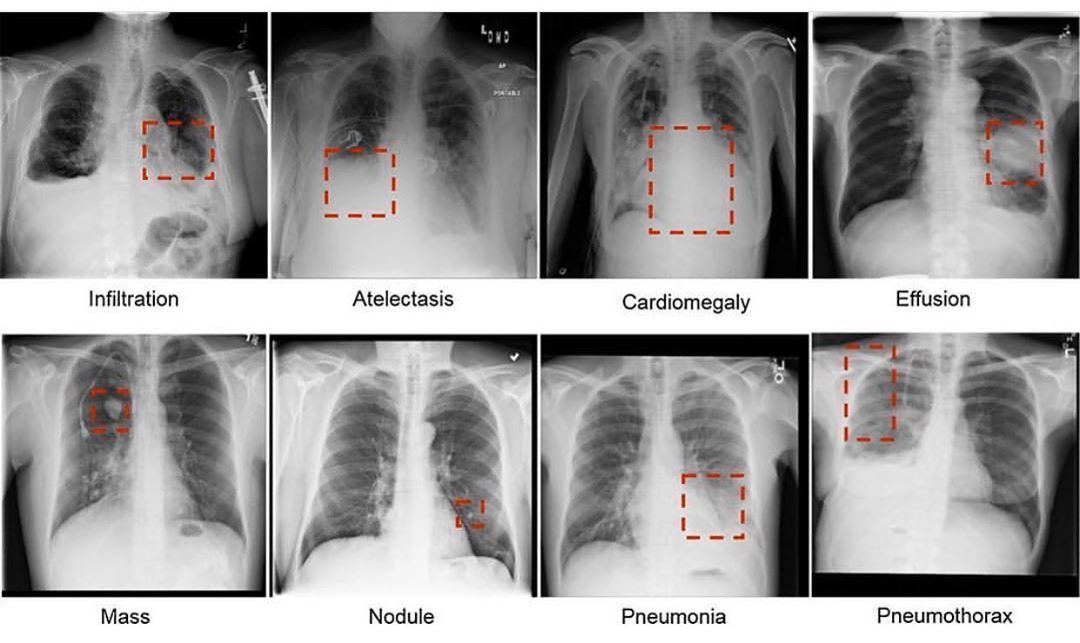

Но одних симптомов недостаточно. Для точной диагностики ателектазов используют целый арсенал методов. Рентгенография грудной клетки — это как карта сокровищ для врачей, где спавшиеся участки легких выглядят как темные пятна. Компьютерная томография (КТ) дает еще более детальную картину, позволяя увидеть даже самые мелкие ателектазы.

Следующий шаг — рентгенография грудной клетки. Это как фотосессия для легких, только вместо гламурных фильтров здесь используются рентгеновские лучи. На снимке ателектазы выглядят как тёмные участки — словно тени на солнечной поляне. Врачи могут увидеть, какие именно области легких решили «прикорнуть» и не участвовать в дыхании.

Но рентген — это только начало. Для более детального изучения может потребоваться компьютерная томография (КТ). Это как если бы вы взяли лупу и рассмотрели каждый миллиметр легких. КТ позволяет увидеть даже самые мелкие ателектазы, которые могли бы ускользнуть от взгляда на обычном рентгеновском снимке.